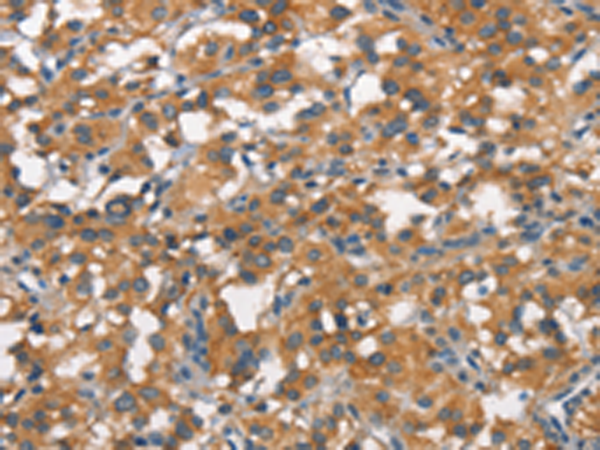

分类: 科研抗体货号: P04322别名: APH; OPH; AARE; ACPH; D3S48E; D3F15S2; DNF15S2应用: WB,IHC反应种属: Human, Mouse, Rat